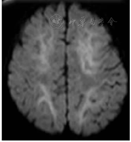

AESD的发病机制目前尚不清楚。由于在日本区域多发,提示其发病有一定遗传倾向性,已经发现相关基因变异及多态性,包括神经元钠通道α1亚单位SCN1A基因发生了错义突变(V982L)及肉碱棕榈酰转移酶Ⅱ(CPTⅡ)基因多态性位点(F352C、V368I、M647V)可能与AESD发病相关[12,13]。神经元兴奋性毒性损伤被认为是导致AESD发病的主要机制之一[14]。血管内皮损伤诱导产生大量炎性因子。在AESD患儿中发现白细胞介素(IL)-6水平升高,脑脊液IL-6升高有助于保护缺血及兴奋性毒性损伤[14],但IL-6与TNF-α可导致严重肝损伤[15]。AESD常出现肝功能异常,其早期AESD指数[天冬氨酸转氨酶(AST)×乳酸脱氢酶/丙氨酸氨基转移酶]即可明显升高,AST多于起病后2周升高最显著,1~2个月后可逐渐恢复至正常水平[15]。AESD患儿常有血清肌酐(Cr)水平升高,并可作为AESD的一个临床危险因素或鉴别点[16]。Cr升高并非代表肾衰竭,至今尚未发现AESD合并肾衰竭的病例,Cr升高的原因可能是兴奋性毒性神经损伤后出现能量供给不足,使脑内肌酸分解供能时产生过多的Cr,同时存在的血脑屏障破坏使其易于释放入血[17,18,19]。过去认为高脂血症是能量不足的代偿反应,与AESD发病机制无关。有研究指出,在头外伤及感染性脑疾患中,高脂血症通常提示预后不良[20,21]。高脂血症诱发脑损伤的可能涉及细胞内酸化、细胞外谷氨酸堆积、脑水肿、血脑屏障破坏等机制[22,23]。高脂血症通过进行性脑血管损伤破坏血脑屏障,内皮细胞基膜是维持血脑屏障完整性关键成分,内皮细胞基膜基质金属蛋白9(MMP9)及基质金属蛋白组织抑制剂1(TIMP-1)在血脑屏障破坏的病理过程中起到重要作用[24]。此外,还有学者提出,脑脊液S100B和tau蛋白作为神经轴突损伤标志也是早期诊断AESD的参考指标之一[25]。急性期脑电图监测到高波幅慢波是AESD的常见表现,但其早期诊断价值仍有争议[26]。AESD典型头部磁共振特点:在病程第1、2天无明显异常,于病程第3-9天出现皮质下白质病灶,呈现"亮树征(Bright tree appearance,BTA)",以弥散加权成像(DWI)更为明显(图1)。磁共振波谱分析(MRS)可见Glx(谷氨酸与谷氨酰胺复合物)升高[27]。早期影像学检查多无异常,对AESD早期诊断帮助不大,但有助于同一些特殊类型脑病的鉴别,如急性坏死性脑病(acute necrotizing encephalitis,ANE)、轻度脑炎/脑病伴胼胝体压部可逆性病变(mild encephalitis/encephalopathy with a reversible splenial lesion,MERS)等[10]。